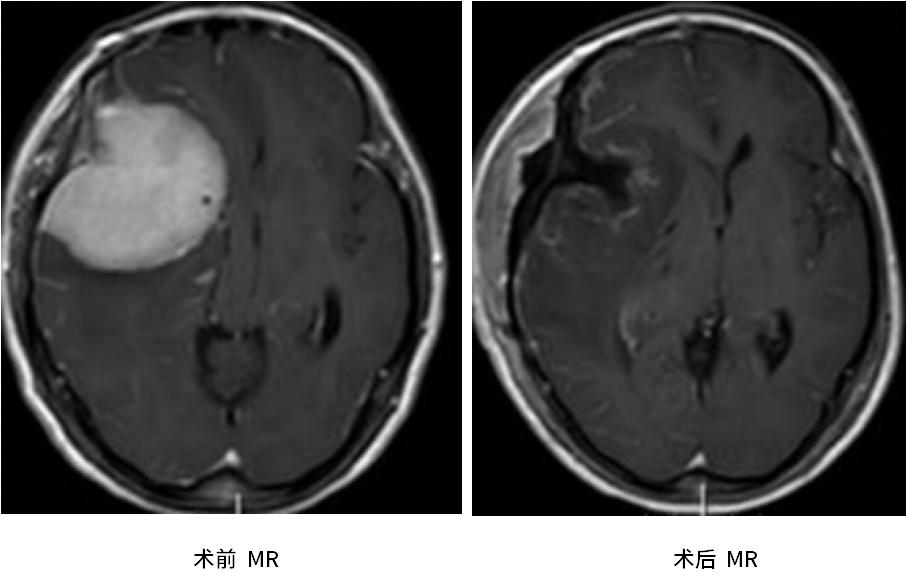

我院神经外十科主任欧阳辉教授接诊后,仔细询问病史及查体,考虑是蝶骨嵴巨大脑膜瘤的可能性大。完善头颅MR及CT脑血管检查后,结果提示患者颅内存在一个病变大小约5.8cm×5.1cm×5.9cm的肿瘤,且右侧大脑中动脉被肿瘤所包绕。

复查MR提示肿瘤全部切除,陈阿姨恢复得良好,一家人终于松了一口气。术后数天,陈阿姨右眼竟奇迹般恢复了视力,看见了眼前的手指,这对于陈阿姨来说也算是意外的惊喜。